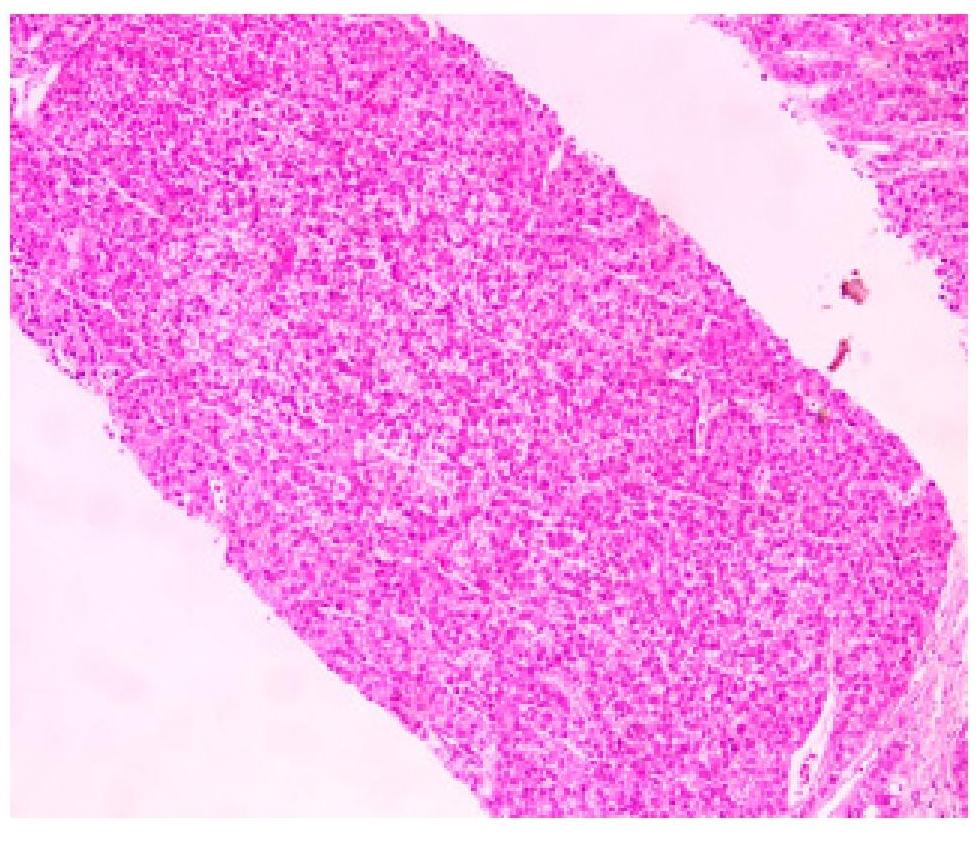

(肝穿刺活检标本)肝细胞肝癌。

免疫组化染色结果:A:CK19(-)、CK8/18(+)、AFP(-)、CK7(+)、Ki67(+,15%)、CD10(- )、CD34(血管+)、P53(灶+)、CEA(-)、HepPar-1(+)。